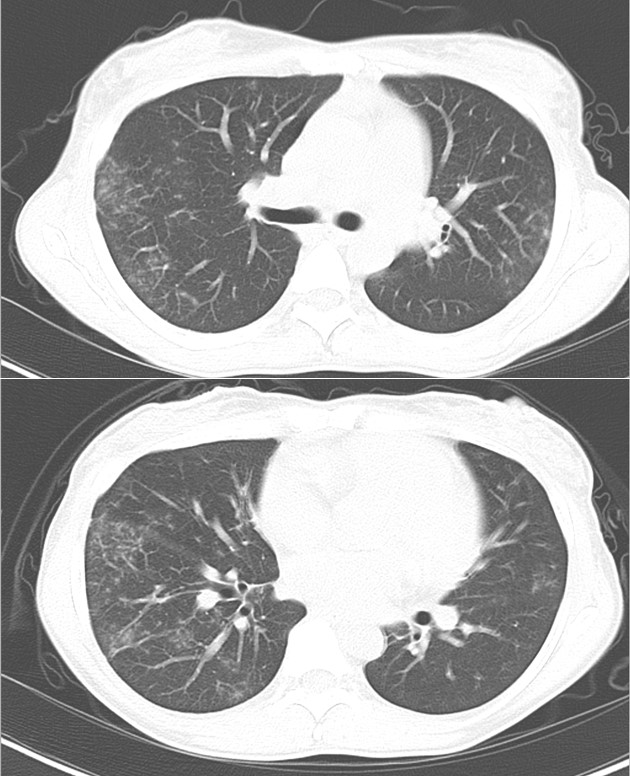

両肺野のすりガラス影の増悪

初診時

第5病日

気管支鏡検査同日よりPSL45mgで加療開始、翌日よりシクロスポリン200mg追加

第25病日

リンパ節の縮小及び肺病変の消退を確認